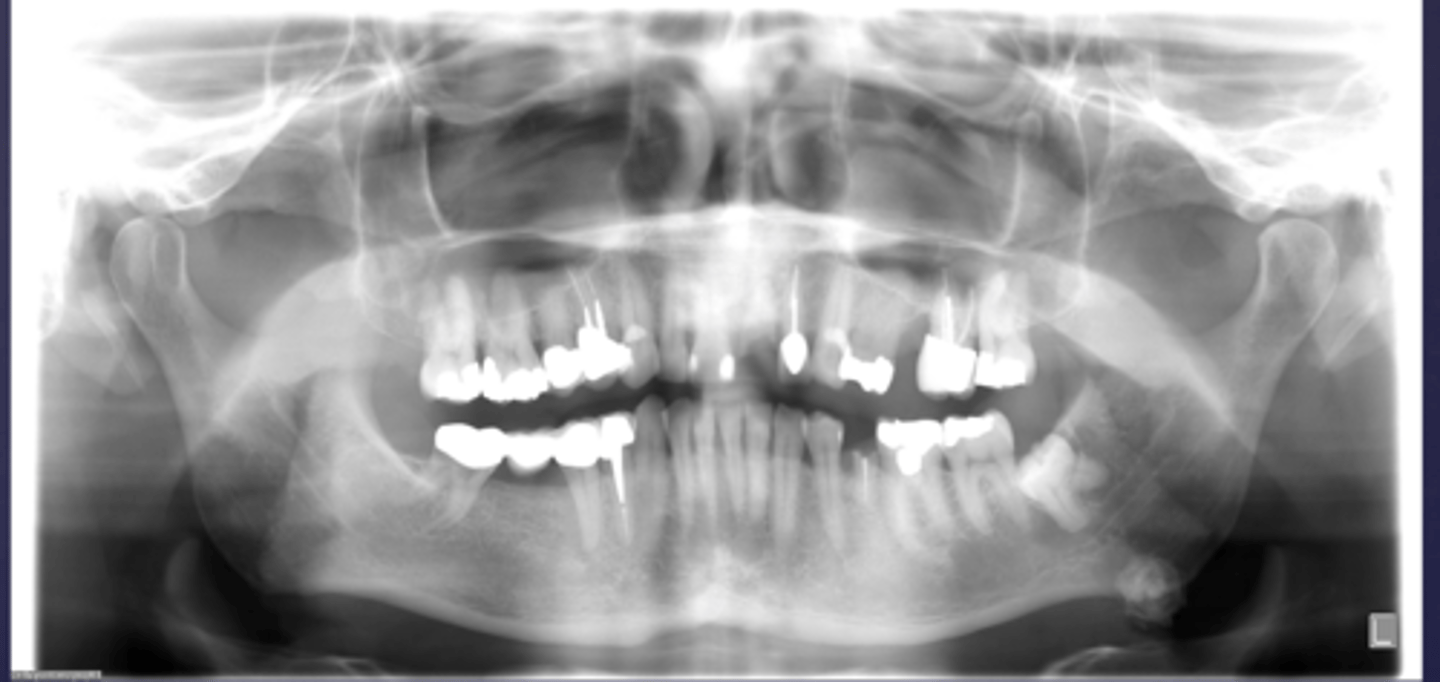

How would you describe the lesion?

- Ill defined, moth-eaten trabecular pattern in the entire mandible

- There is chronic periodontal bone loss associated with most mandibular teeth with furcation involvement and apical radiolucencies

- There is thinning of the inferior mandibular cortex.

- Can also be described as ill-defined areas of mixed radiolucent and radiopacities throughout the

mandible

What category would this lesion be part of?

Inflammation/Malignant

What would be a differential diagnosis for this lesion?

Chronic osteomyelitis

(DD: osteomyelitis, multiple myeloma)